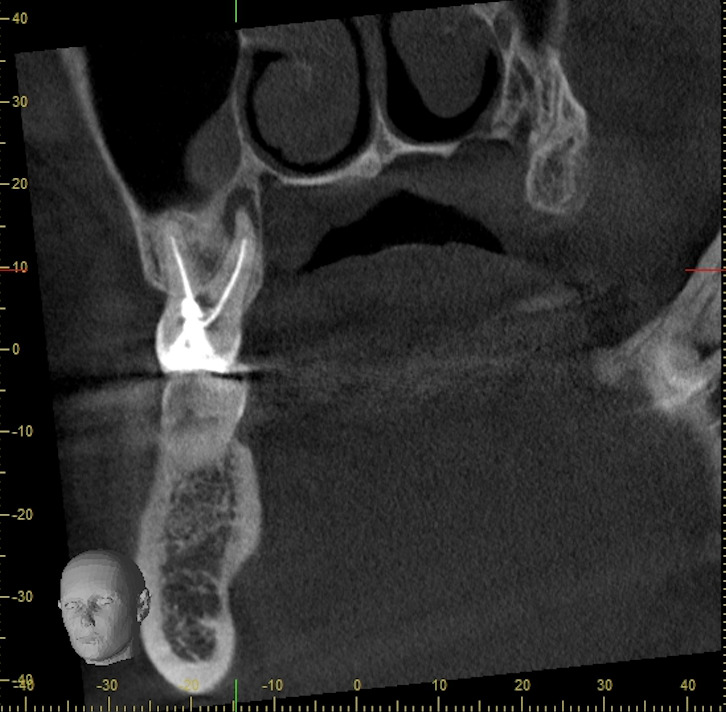

上顎大臼歯にマイクロエンドを行った症例

患者様情報 20代女性 患者様のお悩み 左上の奥歯のあたりが疼く気がする 治療概要 根管治療 提案内容 CTを撮影すると左上の一番奥の歯は神経が壊死しており、その炎症は上顎洞と言われる鼻の横にある空洞まで波及していました […]